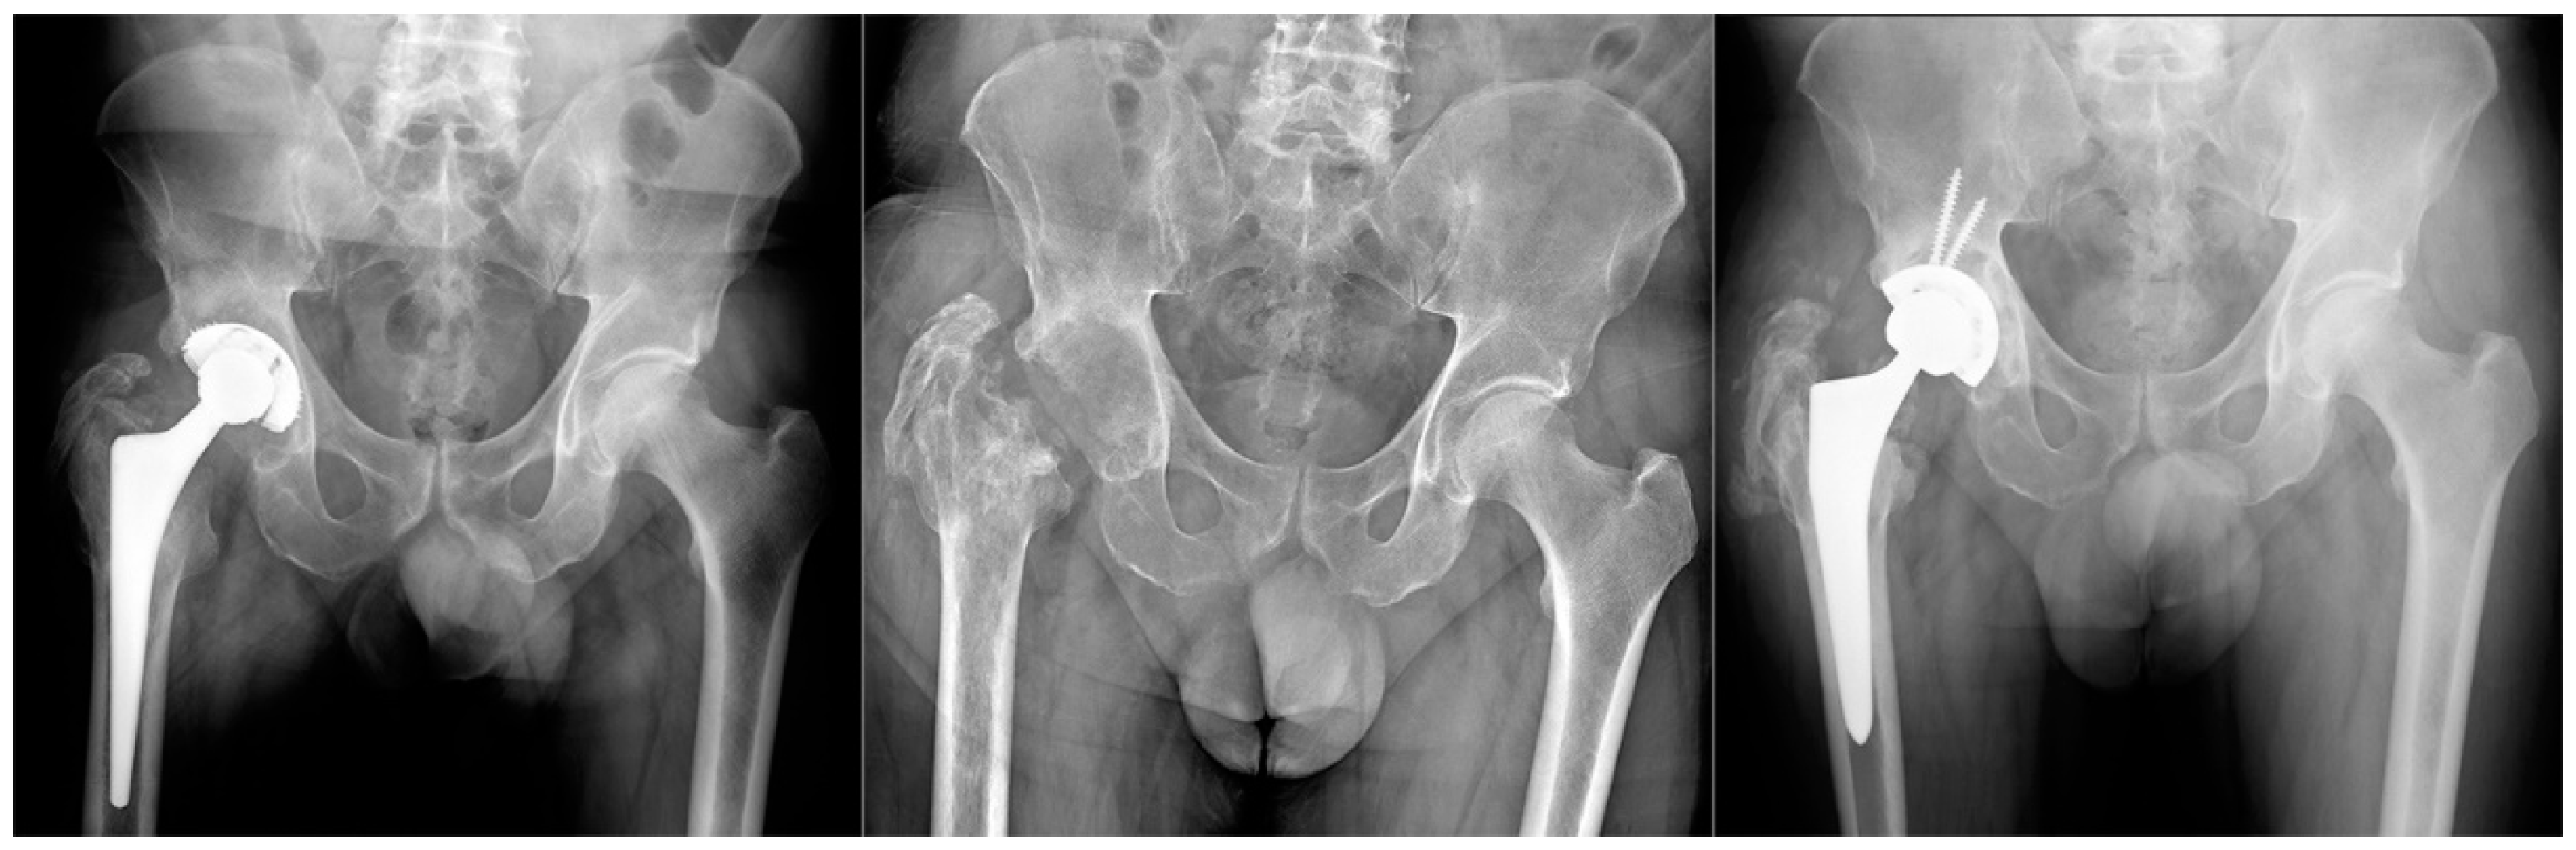

The same procedure was performed in all patients. Patients were explanted and antibiotic therapy was subsequently set up, at first empiric, and then targeted for the isolated pathogen. In no case were antibiotic spacers used. The antibiotic therapy was administered according to the culture sensitivity results. Antibiotic therapy was performed until normalization of CRP following explantation and, in any case, never for more than 8 consecutive weeks. One year after resection arthroplasty was performed, the following two possible outcomes were evaluated: successful TSE arthroplasty was performed in 14 patients (Group A) (Figure 1), and resection arthroplasty without reimplantation in 7 (Group B) (Figure 2). The following were the replanting criteria: CRP normalization with antimicrobial treatment in at least two controls separated by two weeks. If normalized, antibiotic therapy was discontinued, patients were then monitored for an additional 4 weeks by weekly CRP checks. If the latter remained normal, labeled leukocyte scintigraphy was done. If the latter was also negative, reimplantation was scheduled, which was to be performed only after intraoperative negative histology.

Figure 1.

Group A Patient affected by chronic PJI treated with TSE. The patient was eligible for reimplantation after 4 month targeted antimicrobial therapy. After 12 months follow up there were no signs of recurrence of infection.